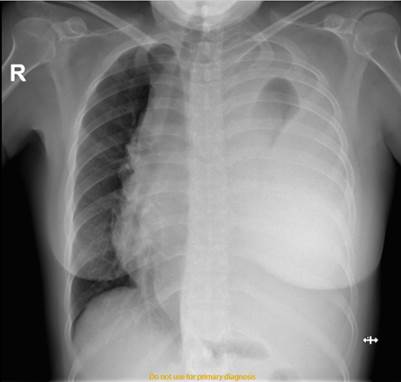

Figura 5:  TAC de tórax con contraste, llama la atención a nivel de mediastino superior y anterior gran masa sólida, isodensa heterogénea, mide aproximadamente 18 x 10 x 9 cm, áreas de necrosis en su interior. Corazón de tamaño y morfología normal.

Imagen tomada de: Caso Clínico Clínica Abendaño.  Loja - Ecuador

Figura 6:  TAC de tórax, Presencia de masa mediastinal, colapso pulmonar izquierdo, derrame pleural izquierdo masivo. Tráquea desplazada hacia la derecha.

Se sugirió la realización de una tomografía contrastada para mejor caracterización de la lesión, en la que se especifica la presencia de masa sólida a nivel de mediastino superior y anterior, isodensa heterogénea con áreas de necrosis en su interior, que al administrar medio de contraste existe captación, con medidas de 18x10x9 cm (Fig. 5), el mismo que desplaza las estructuras del mediastino hacia la derecha y diafragma izquierdo hacia caudal, se observa que engloba vasos sanguíneos. Se Observa asimetría de campo pulmonar, con colapso de pulmón izquierdo, determinando la presencia de derrame pleural izquierdo severo. (Fig. 6)